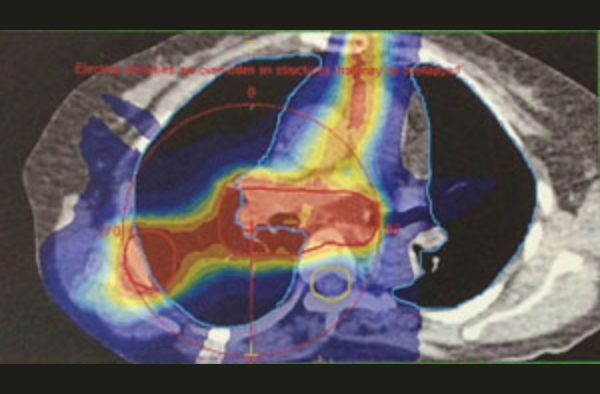

直腸がん+右骨転移

放射線治療中の動画の確認(必要時に行う)

大線量が放出されている脇で

CTを撮影して腫瘍位置を検証